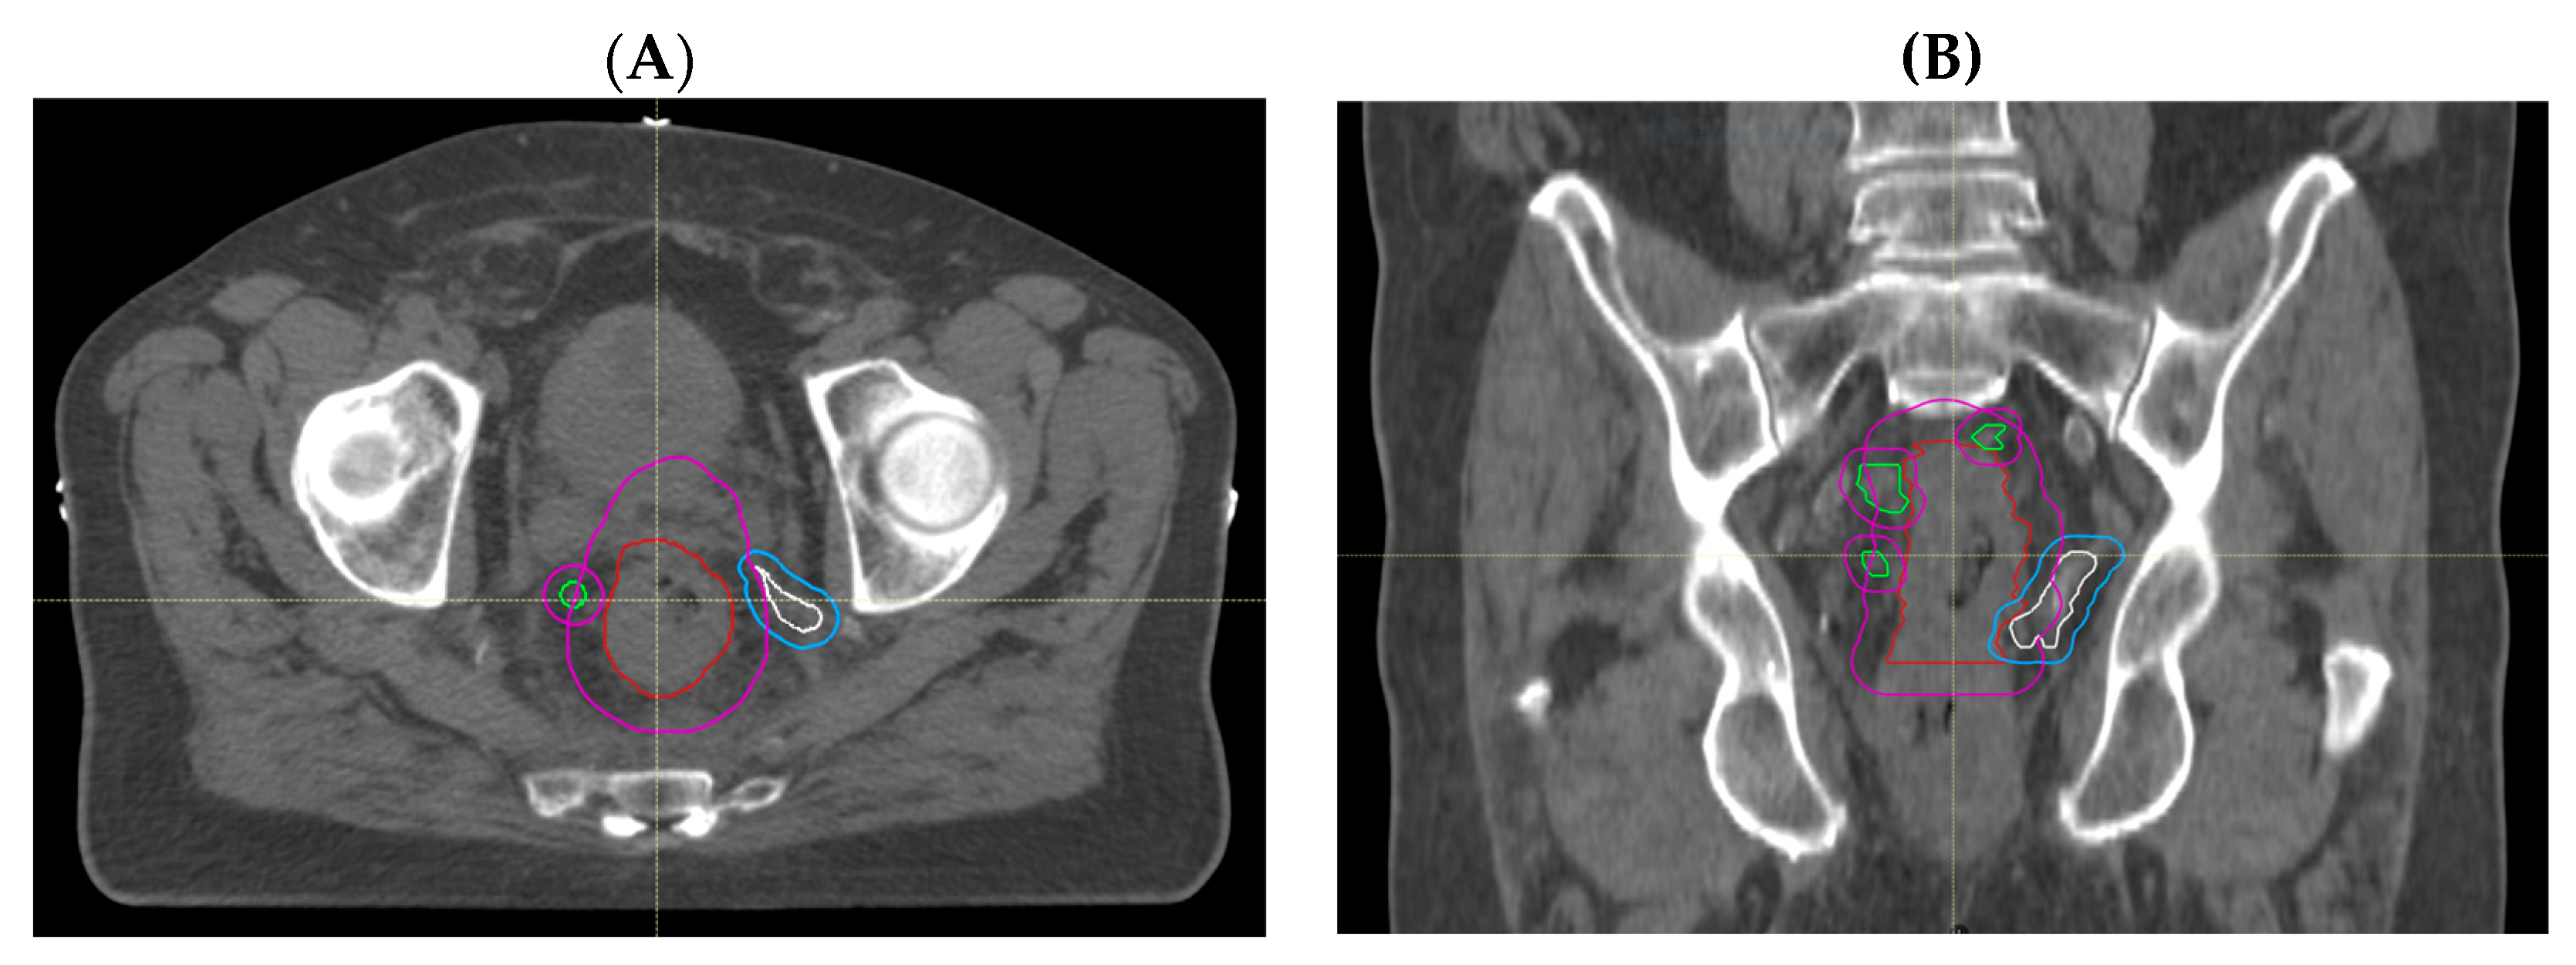

Through treatment volume comparisons, we observed no GTV geographical miss in any of the primary tumours that were all adequately encompassed. However, we observed that delineation of involved lymph nodes and areas of EMVI was more likely to represent sources of uncertainty. Nodal GTV geographical miss in the high-dose boost volume was evident in 5 out of 27 patients (19%); of these, 4 cases (15%) had missed mesorectal nodes that were encompassed in the PTV45Gy, but one node involving the pelvic side wall was outside of the treatment volume in the remaining patient (Figure 2A,B). EMVI GTV geographical miss occurred in 2 out of 27 (7%) patients (Figure 3A,B). These areas of EMVI were both encompassed in the PTV45Gy. Taken together, these results show proof of concept that an adjustment of MRI reporting to highlight the exact extent and location of macroscopic disease, in particular nodal involvement and EMVI, has the potential to improve the accuracy of radiotherapy volume delineation.

Figure 3.

Radiotherapy planning CT showing EMVI GTV geographical miss. (A) Sagittal view and (B) coronal view illustrating an area of contiguous EMVI (white) with its corrected CTV (blue) extending outside the treated CTV (magenta), with GTVp (red) and GTVn (green) as depicted.